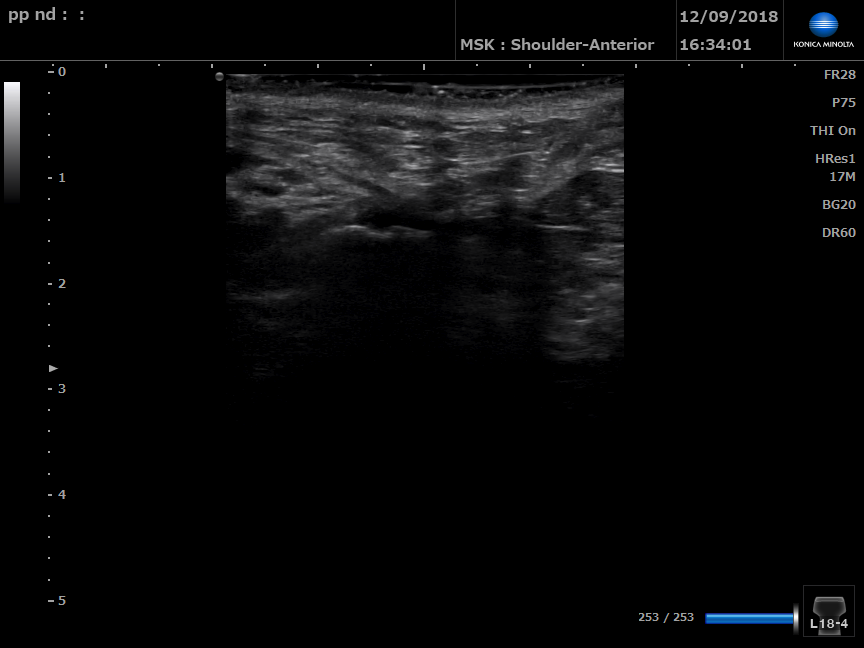

B Mode ultrasound of left perineal body

B Mode ultrasound of right perineal body